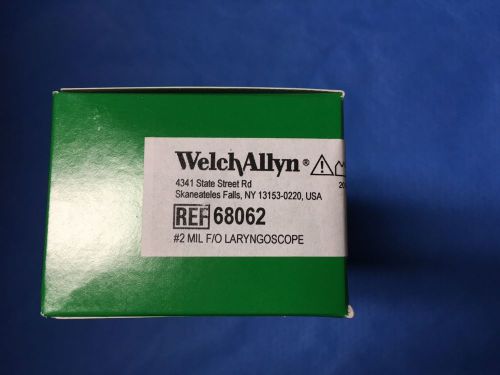

Welch Allyn 68062 Fiber Optic Laryngoscope Blade - Miller - Size 2 - NEW